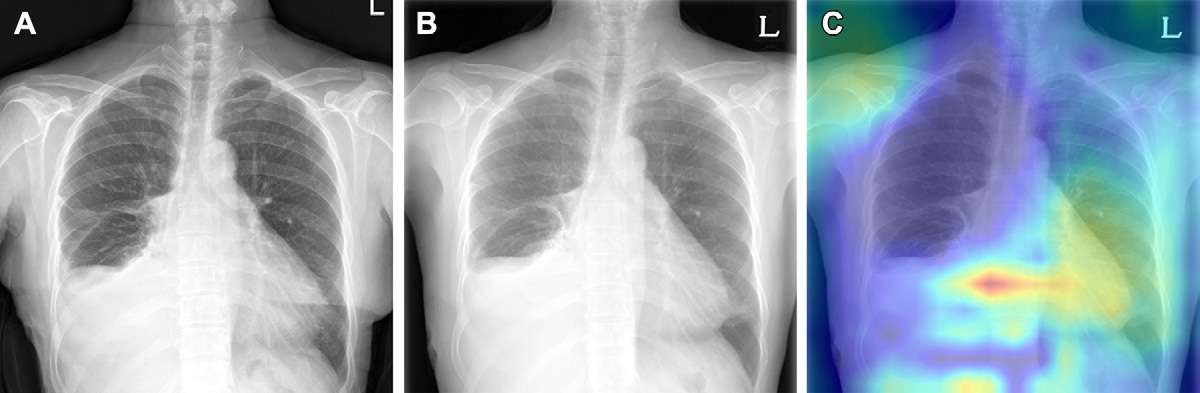

The AI model is an encoder-decoder model trained to generate a text report given a chest x-ray and most recent comparison (anterior-posterior or posterior-anterior view only). The vision encoder weights were initialized from Vision Transformer (ViT) base and the text decoder weights were initialized from Robustly Optimized BERT Pretraining Approach (RoBERTa) base before training for 30 epochs on a data set of 900,000 chest x-rays (CXRs). cp indicates chest pain; sob = shortness of breath. Image courtesy of JAMA Open Network.